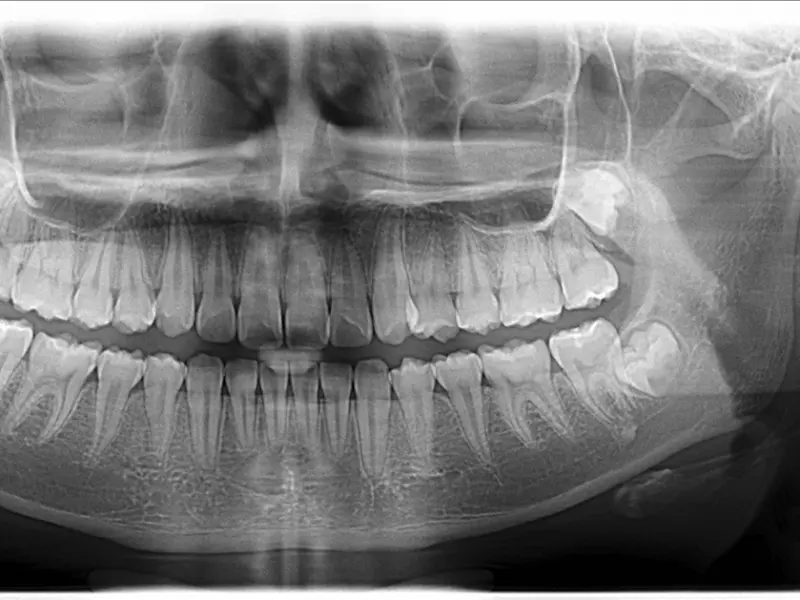

Pacjent D.B., lat 34, zgłosił się do gabinetu w celu przeprowadzenia szczegółowego badania przeglądowego. Nie zgłaszał żadnych dolegliwości ze strony zębów. W badaniu stwierdzono klinicznie prawidłowe wszystkie wypełnienia i uzupełnienia, z wyjątkiem korony z porcelany napalanej na metal na zębie 46, o nieszczelnym pobrzeżu, masowym przecieku bakterii oraz miejscach gromadzenia się płytki zarówno w okolicy mezjalno-policzkowej, jak i dystalno-policzkowej. Badanie radiologiczne potwierdziło niezadowalające pobrzeże korony. Dodatkowo stwierdzono, że w kwadrantach 1. i 4. było wiele wypełnień o zaskakująco grubej warstwie i niskiej przezierności. W tego typu przypadkach diagnostyka różnicowa obejmuje możliwość obecności linera o znacznym stopniu przezierności, grubej warstwy systemu łączącego albo próchnicy wtórnej. Ząb 15 wykazywał dodatkowo w okolicy dystalno-zwarciowej przebarwione pobrzeże wypełnienia, dlatego zdecydowano się przeprowadzić w nim leczenie odtwórcze i zarazem eksploracyjne, od którego uzależniona był decyzja, czy pozostałe podejrzane zęby należy objąć leczeniem, czy też obserwować.

• Indywidualna pełna diagnostyka radiologiczna jamy ustnej: 4 zdjęcia skrzydłowo-zgryzowe, 8 zdjęć zębowych, 1 zdjęcie pantomograficzne.

Pacjent zgłosił się na wizytę w celu przeprowadzenia szczegółowego badania przeglądowego. Po stwierdzeniu podejrzanych zmian w kwadrancie 1. i 4. poinformowano pacjenta, jakie mogą być potencjalne scenariusze. Obszary zwiększonej przezierności poniżej istniejących wypełnień kompozytowych należy poddać diagnostyce różnicowej, uwzględniając: grubą warstwę podkładu szkło-jonomerowego modyfikowanego żywicą, grubą warstwę systemu łączącego, pozostawione tkanki próchnicowe oraz próchnicę wtórną. Podjęto decyzję o eksploracyjnej odbudowie zęba 15 na powierzchni dystalnej i zwarciowej, mając na uwadze identyfikację problematycznego materiału.